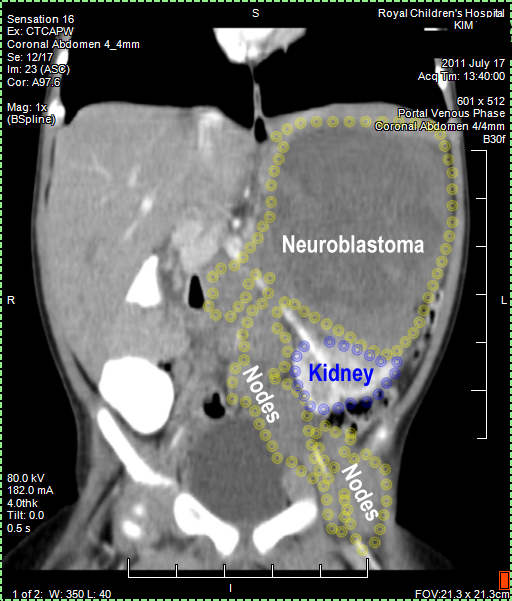

Kim's Neuroblastoma IV,

N-Myc amplification

CT (CAT) scan 17July 2011